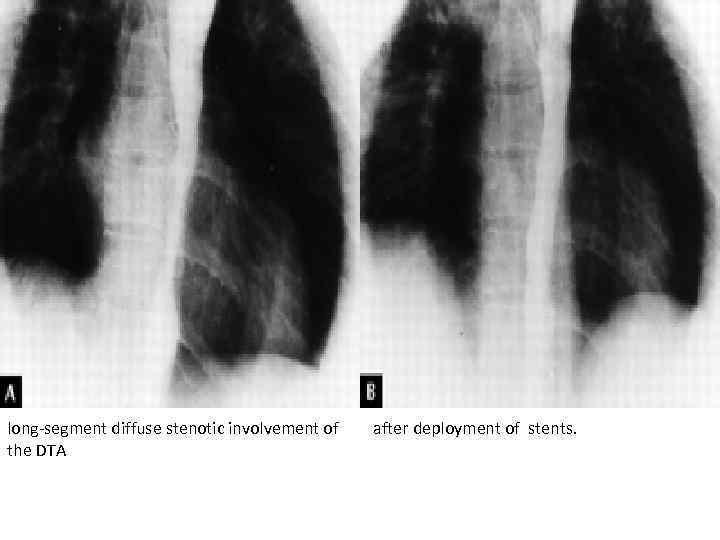

long-segment diffuse stenotic involvement of the DTA after deployment of stents.